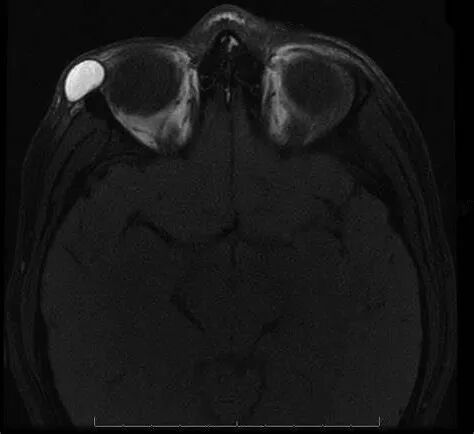

眉弓皮样囊肿通过医生的体格检查即可诊断,影像学检查可对该病的诊断提供重要支持。超声检查对评估囊肿的大小、范围、囊内容物的性状有一定帮助。CT即可看到囊肿又可显示骨骼,对于评判囊肿与颅骨的情况有重要意义。MRI检查则更有利于观察囊肿与眼眶周围软组织的关系。